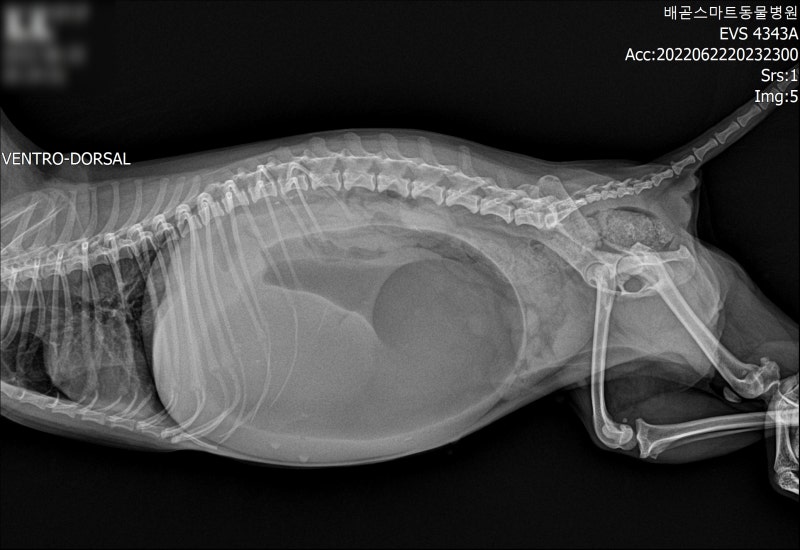

✅ 진단

- 복부 X-ray (위의 팽창 및 꼬임 확인)